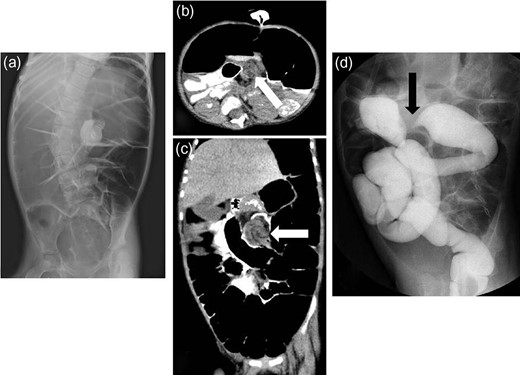

A 3-year-old boy was admitted with bilious vomiting. Abdominal X-ray films showed a gasless abdomen (Fig. 3a). Enhanced CT findings were consistent with duodenal obstruction (Fig. 3b and c). A barium meal revealed malrotation and it was difficult to insert an enteral feeding tube into the small intestine (Fig. 3d). He underwent a laparotomy, and the intra-operative findings revealed Ladd’s bands associated with mesenterium ileocolicum commune and malrotation of the intestine (Fig. 4a and b). He underwent division of the abnormal bands tethering the duodenum, which caused extrinsic compression, widening of the mesenteric base to prevent a further volvulus, and an appendectomy. He is currently doing well without a recurrence.

Radiologic findings from Case 2. (a) Abdominal X-ray films showing a gasless abdomen. (b and c) Enhanced CT showing a suspected duodenal obstruction (black arrow: suspected lesion). (d) Barium meal revealing malrotation and difficulty inserting the enteral feeding tube into the small intestine (white arrow: the tip of the tube).